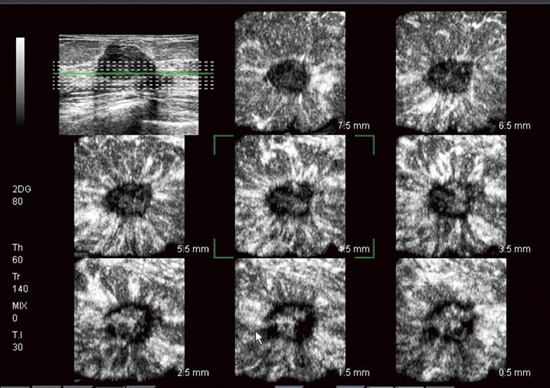

●新たな断面の観察を可能に:4Dイメージング

高周波4Dプローブを使ってボリュームスキャンを行い,直交3断面や一定スライス間隔の複数断面(MultiView)が表示可能なほか,体表に水平な断面像(Cモード)を観察可能です。さらに,ボリュームデータをポジネガ反転して構築するCavityモードにより,乳管の走行や嚢胞の形状がより把握しやすくなります。 |

4Dプローブで連続した多断面を観察